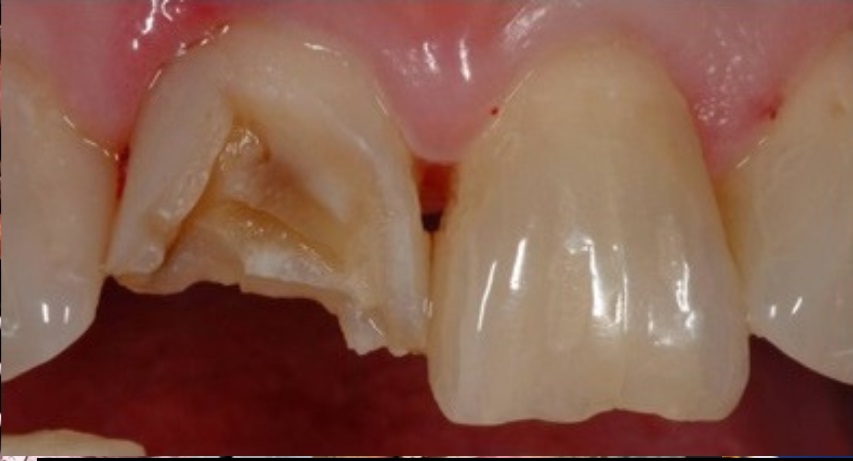

Tooth is Broken

- Find the piece of tooth that broke off if possible.

- Put the piece of tooth into a cup of water or milk.

- See the dentist ASAP, within 24 hours, and bring the broken piece to the dentist. This piece may be able to be used and reattached.

- Take OTC Tylenol or ibuprofen if needed.